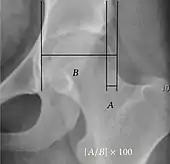

- Reimer's migration index (MI), also called the femoral extrusion index,[3] is calculated if hip dysplasia is detected. It can be used to indicate hip dislocation. It is the horizontal distance (parallel to the Hilgenreiner Line) between the Perkin line and the lateral border of the ossification center of the femoral head, divided by the horizontal width of the ossification center. The migration index is normally less than 33% by most sources,[9] but 25% and 30% has also been suggested.[10]